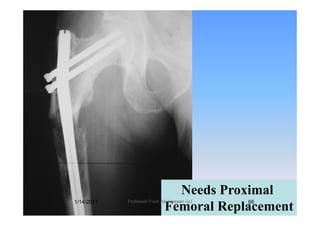

Subtrochanteric fractureSubtrochanteric fracture

Reconstruction nail with locking

l th f l kscrews along the femoral neck.

reduces the risk of subsequent NOF fracturereduces the risk of subsequent NOF fracture

if th f t f il t it i tiif the fracture fails to unite, persisting

pain may result in revision surgery orpain may result in revision surgery or

even Proximal Femoral Replacement.p

Needs ProximalNeeds Proximal

Femoral Replacement